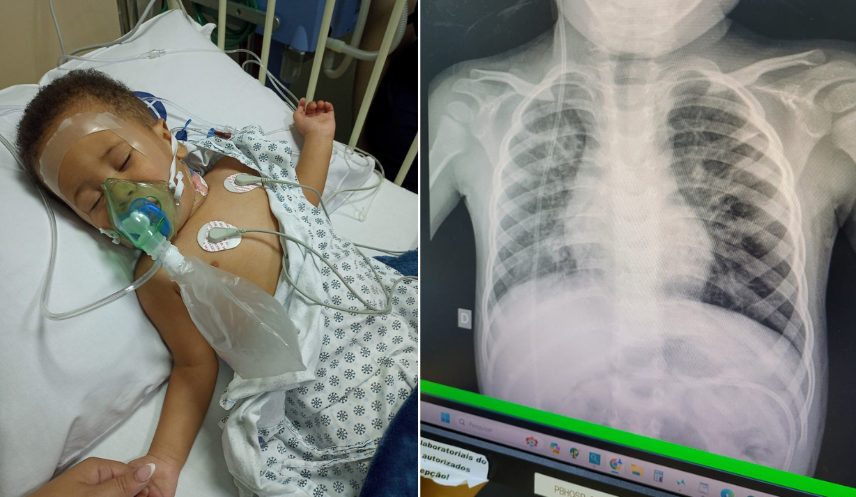

Théo, de 3 anos, é um pequeno sobrevivente que nasceu prematuro extremo e hoje lida com condições de saúde muito complexas. Vive com a família no Rio de Janeiro e passam por dificuldades.

O quadro dele envolve 5 diagnósticos graves: broncodisplasia pulmonar, o que significa que seus pulmões possuem áreas "mortas" ou com cicatrizes (fibrose), fazendo com que ele precise de um aparelho para respirar enquanto dorme.

Ele também convive com a hidrocefalia (acúmulo de líquido no cérebro), que é controlada por uma válvula interna, e com a paralisia cerebral, que afeta seus movimentos e o fez perder a capacidade de andar que havia conquistado anteriormente

Além disso, o Théo enfrenta a epilepsia e um quadro de autismo que gera crises intensas de autoagressão.

Como ele não consegue mais se alimentar pela boca, ele utiliza uma sonda ligada diretamente à barriga (gastrostomia) para receber seus nutrientes.